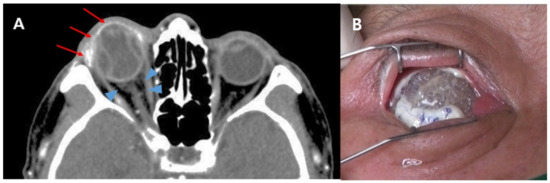

3.2. Risk Factors for Orbital Implant Extrusion after Evisceration

4. Discussion